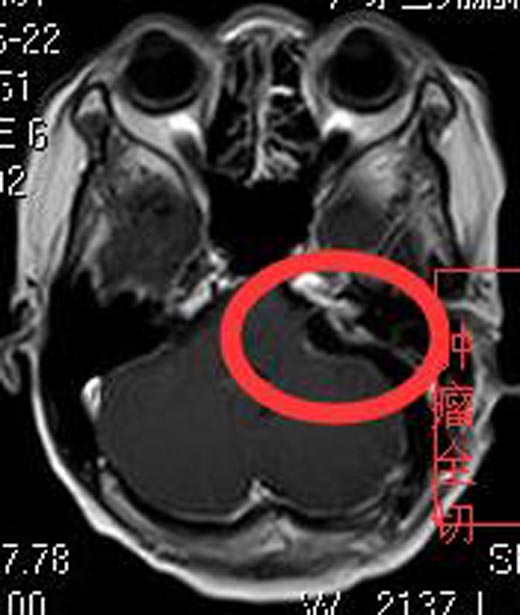

入住广东三九脑科医院综合神经外科,头颅MR检查提示:左侧桥小脑角区占位性病变,大小约为4.4cm×3.3cm×2.4cm,考虑听神经鞘瘤。头颅CTA检查提示:左侧桥小脑角区占位病变,其内血管丰富,考虑听神经瘤可能。

完善术前检查后,由鲁明主任主刀,在全麻下行左侧桥小脑角区占位切除术,术中显微镜下见肉红色肿瘤组织,包膜完整,被小脑前下动脉包绕,血供丰富,显微镜下见肿瘤上至三叉神经,下达末组颅神经,与面听神经及脑干明显粘连;予分块全切除肿瘤,相邻神经、血管保护满意,面听神经解剖保留,手术过程顺利。术后黄阿姨没有面瘫、嘴角歪斜、饮水呛咳等后组颅神经损害症状,听力明显好转,康复出院。术后病理结果提示:神经鞘瘤。